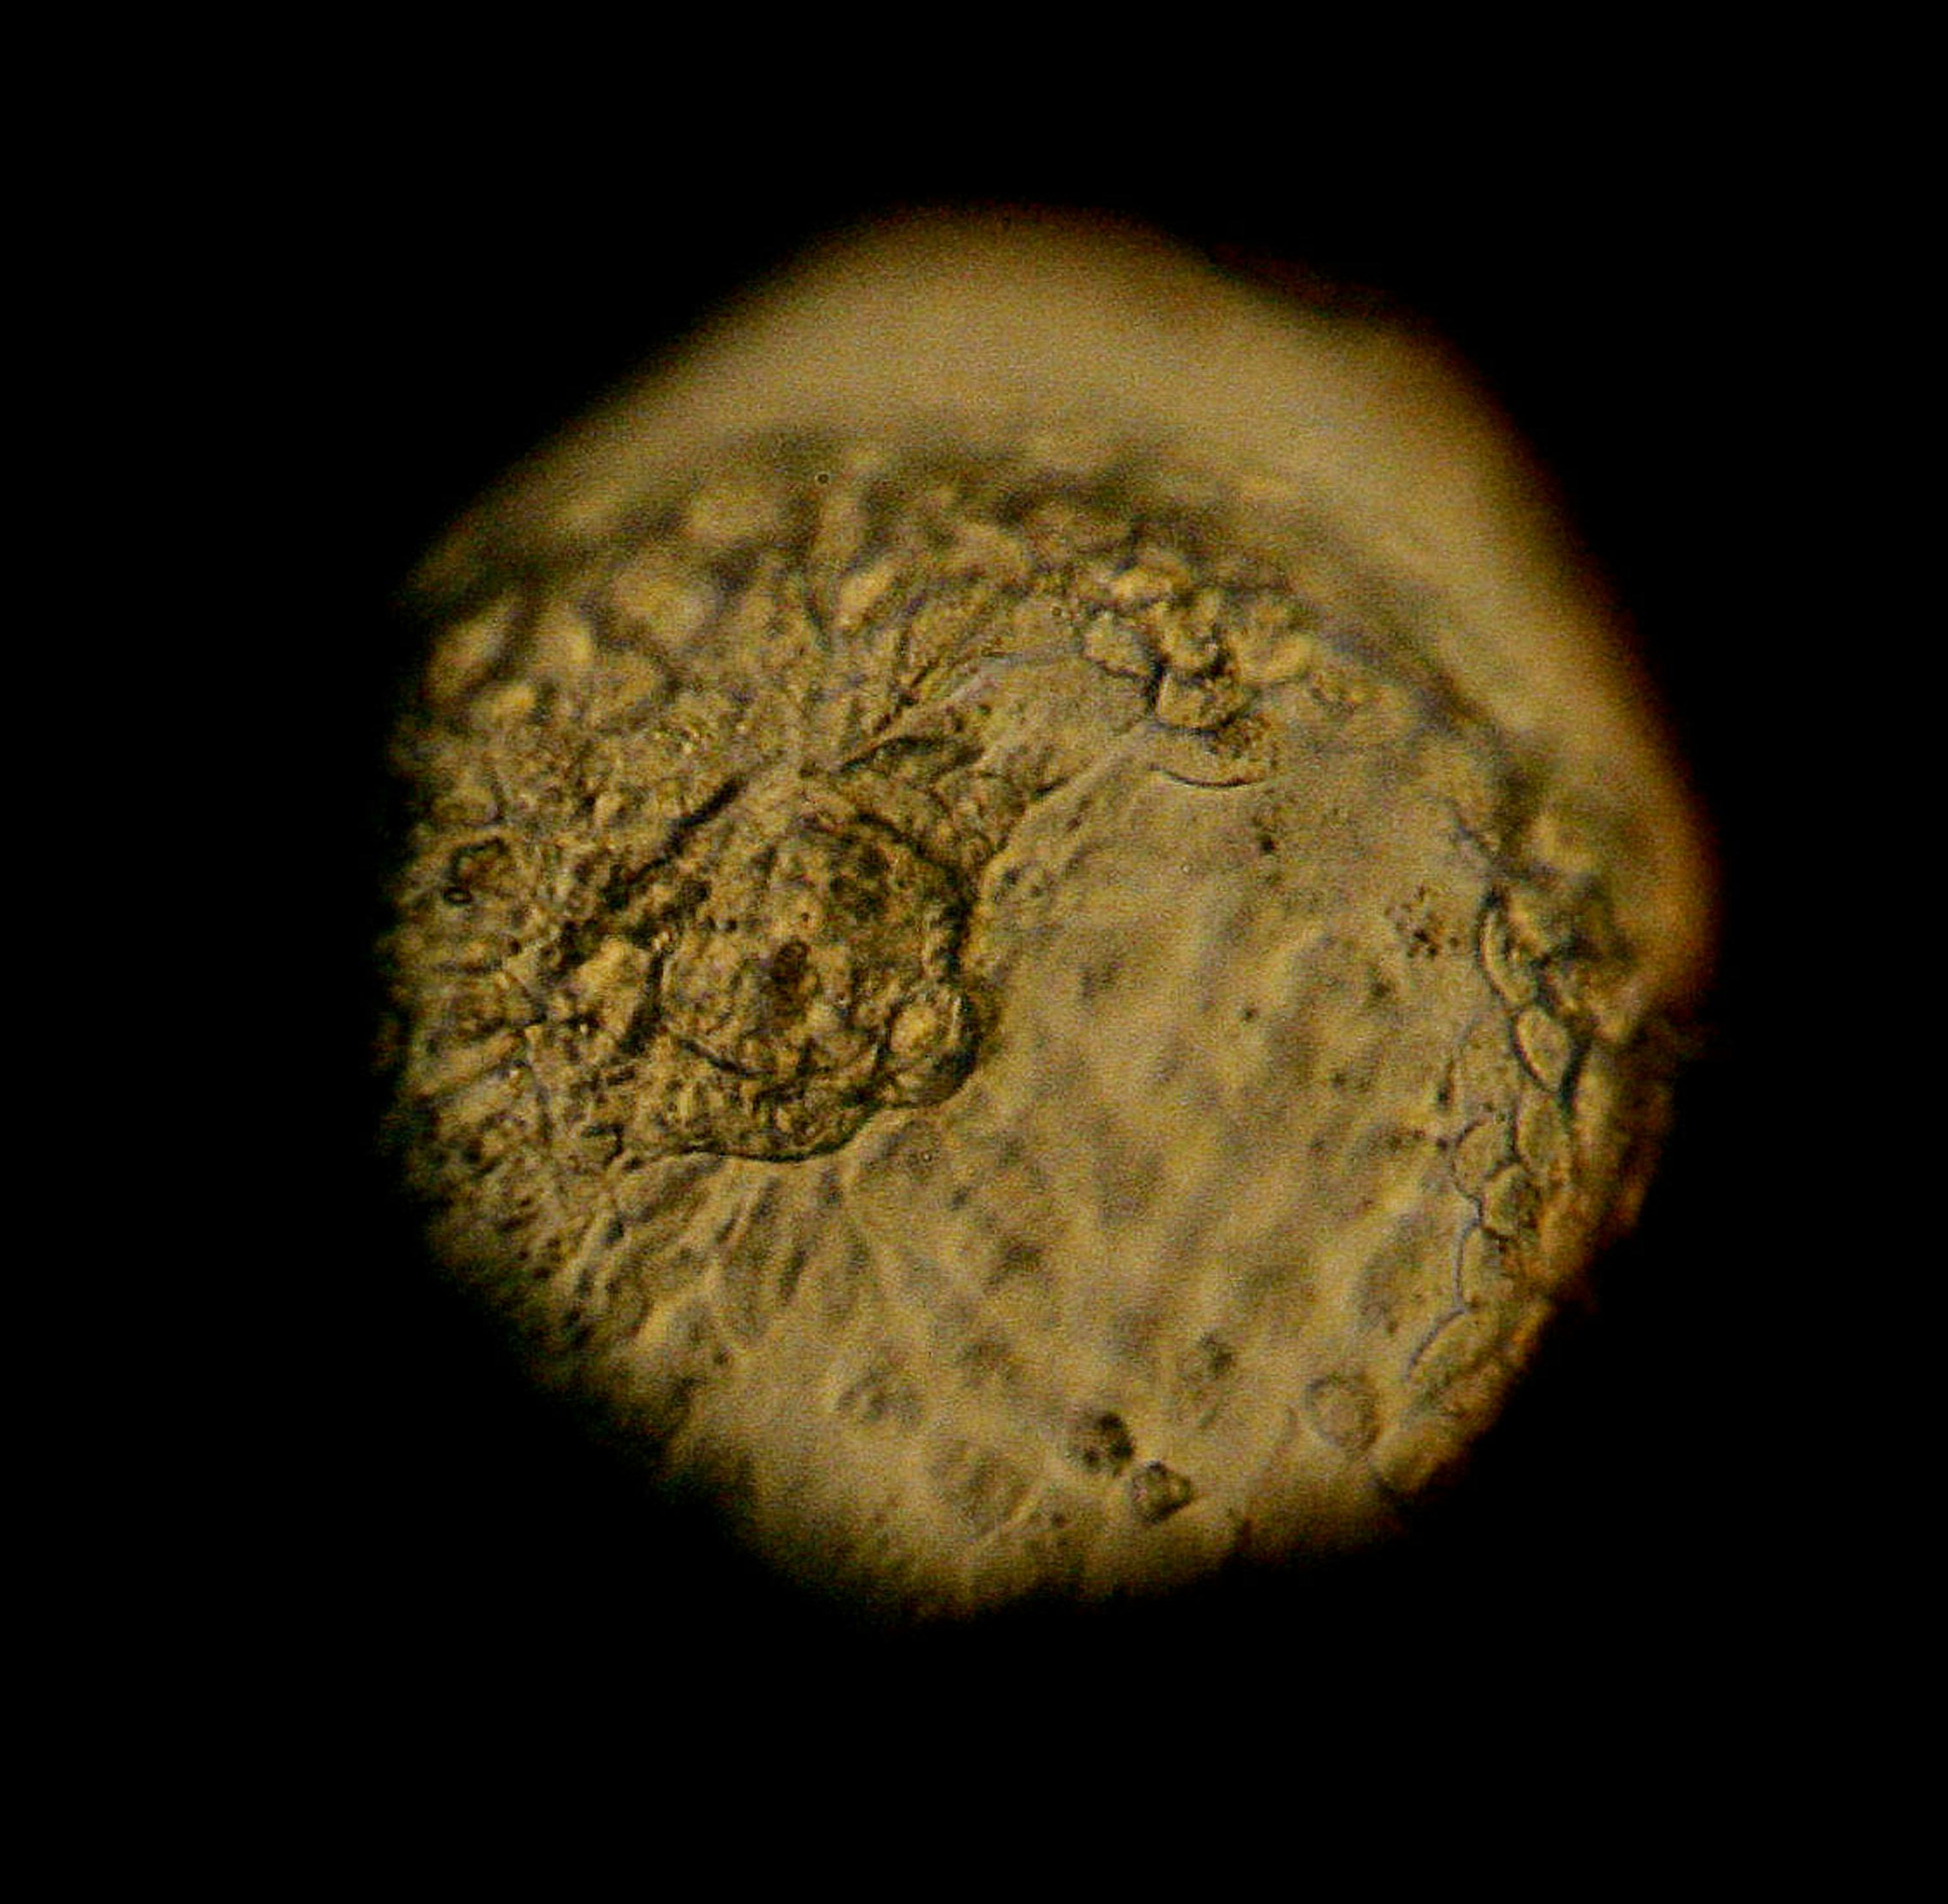

Embryo Frozen For 24 Years . A baby has been born from an embryo frozen for. the parents of a baby girl, who grew from an embryo frozen for 24 years, are calling her birth a miracle. the embryo, created from anonymous donors, was frozen on october 14, 1992, just one year after mother tina gibson's own birth. a tennessee woman has given birth to a daughter who spent 24 years as a frozen embryo — making the baby the longest. but what makes emma a miracle child? a tennessee couple has welcomed a baby girl who grew from an.